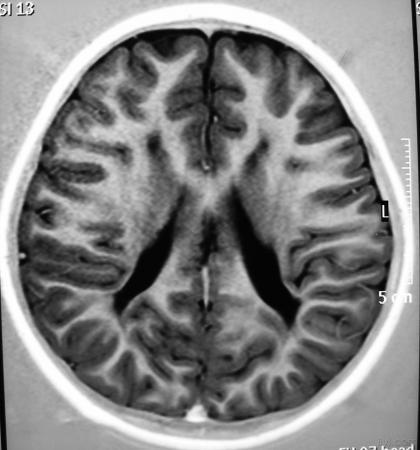

影像学发生于侧脑室周围,侧脑室扩大,脑白质减少。扩大的侧脑室外缘常不规则为其特点,多为双侧脑室同时扩大。脑白质减少,脑皮层与脑室侧缘相近。MRI T1呈低信号,T2呈高信号。